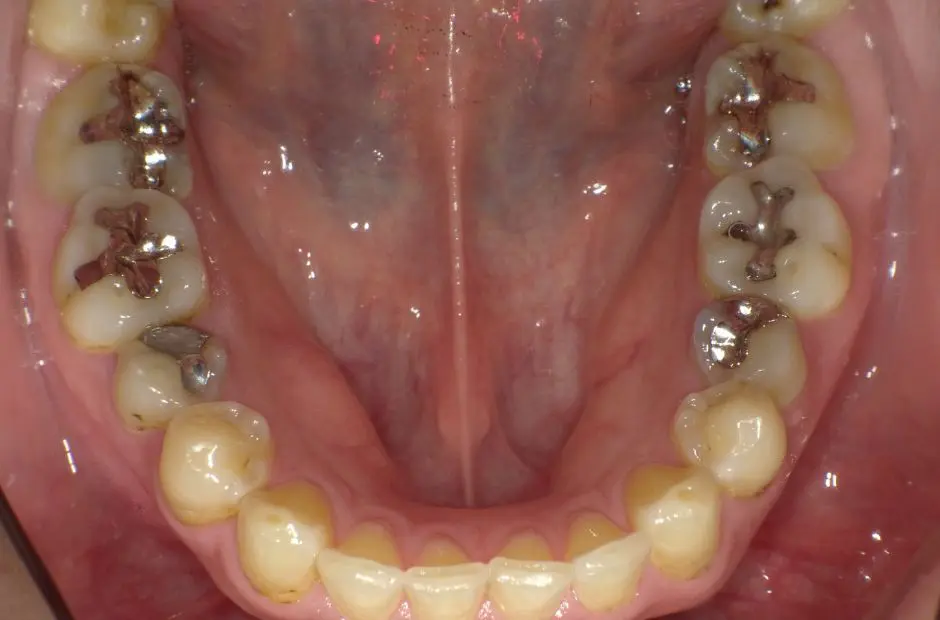

case.02

金属アレルギー治療の症例・治療前写真(銀歯7本)

金属アレルギー治療の症例・治療後写真(銀歯7本)

「 メタルフリーで、健康を手に! 」

当サロンのメタルフリー治療は、金属アレルギーの心配を排除し、健康な口内環境を実現します。高品質な非金属素材で安心と健康を手に入れましょう。

治療内容 古い銀歯を取り除き、レジンとセラミックを組み合わせて装着

治療期間/回数 2ヶ月/通院6回

施術当時の総額 220,000円(税込。検査・診断・手術関連処置費用などは含まない)。e-maxインレー:55,000円/1カ所

リスク・副作用 咬合による割れ